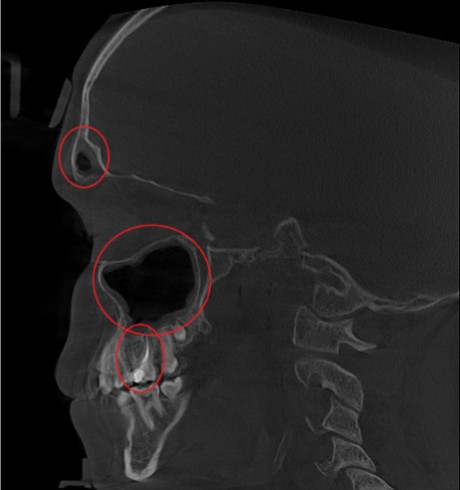

Проведена компьютерная томография околоносовых пазух, которая подтвердила наличие правостороннего гемисинусита (воспаление нескольких пазух с одной стороны), как следствие периодонтита зуба 1.6.

Представлено КЛКТ околоносовых пазух до начала лечения. Выделена зона воспаления пазух.

На снимке детально представлена область пораженного зуба 1.6.